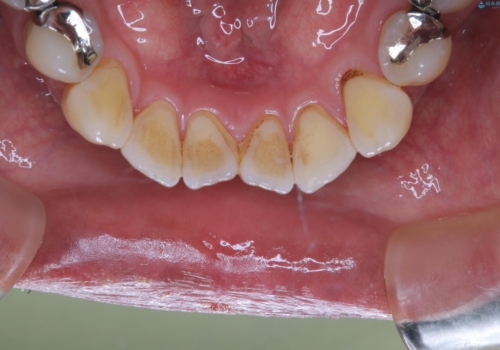

- クリーニングをしてほしいとのことで来院されました。

PMTC60分コースを行いました。

着色がとても多くついていました。